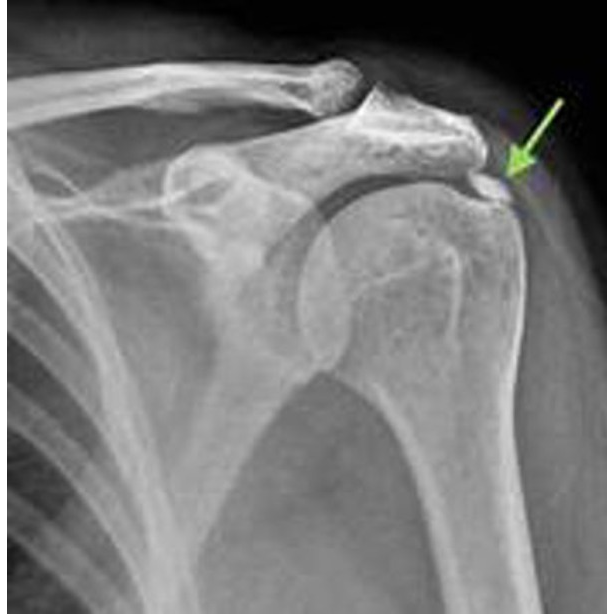

Calcification of the Supraspinatus Tendon: Cause of Pain or Incidental Finding?

Calcification of the supraspinatus tendon is a common finding on imaging studies, especially in individuals with shoulder discomfort. However, it's important to understand that not all calcifications are painful. In many cases, these are incidental findings that may not be the true source of the patient's pain.

The actual pain often stems from surrounding muscle spasms, inflammation, or mechanical dysfunction in the rotator cuff and shoulder joint. Misidentifying the source of pain can lead to unnecessary interventions and prolonged discomfort.